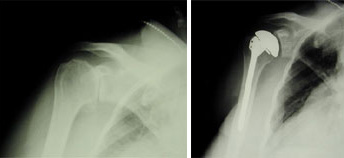

(Left) An x-ray of a healthy shoulder joint. (Right)Osteoarthritis of the shoulder. Note the the decreased joint space in the x-ray (arrow).

A total shoulder joint replacement.

These x-rays were taken before and after total shoulder replacement surgery for osteoarthritis.